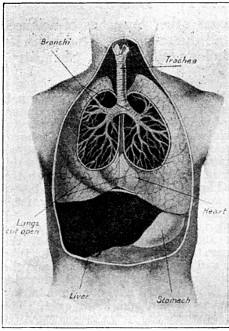

ITS STRUCTURE—ORGANIZATION INTO SYSTEMS—FUNCTIONS—SPECIAL SENSES—NERVOUS SYSTEM—PERSONAL HYGIENE—PREVENTION OF DISEASE—INTERDEPENDENCE OF BODY AND MIND—EUGENICS—ILLUSTRATIONS AND CHARTS.